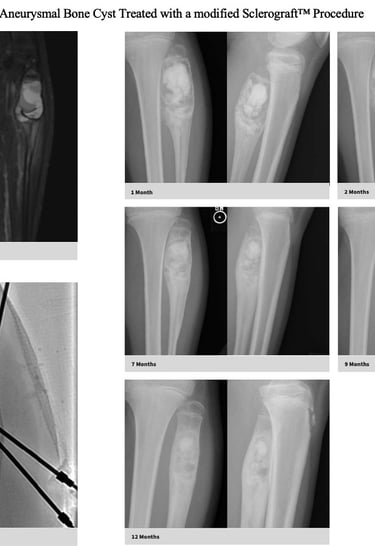

Gallery

Explore our educational resources and images

The Sclerograft procedure is a minimally invasive outpatient procedure used to treat bone cysts.

Utilizing needles, chemical sclerosis destroys the cyst wall and regenerative bone graft is injected via the needles to expedite bone healing.

The doctor uses imaging guidance (like X-ray or ultrasound) to guide needles into the cyst.

Chemical sclerosis using chemicals like doxycycline are washed through the cyst to kill the cyst wall lining

Regenerative bone graft is then injected through the needles and the needles are removed. The bone graft is temporary and is eventually reabsorbed by the body.

Quick recovery and bone formation seen between 6 weeks to 3 months

Proven success in both UBCs and ABCs